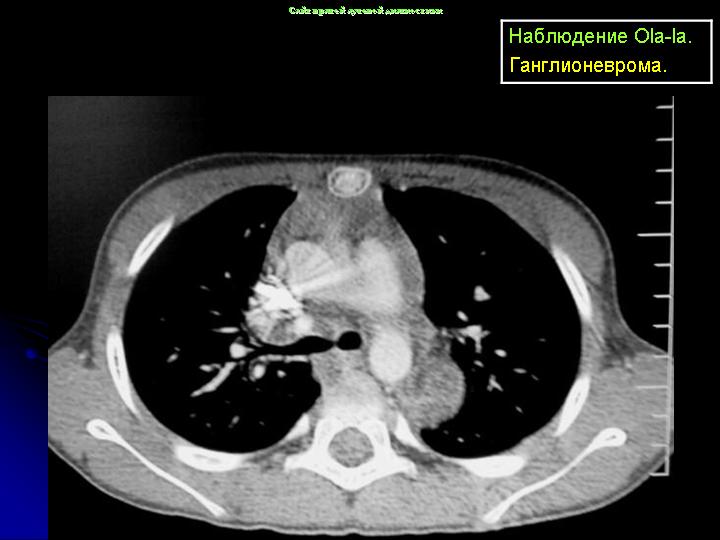

Онкология. Ганглионеврома. +

Ганглионеврома.